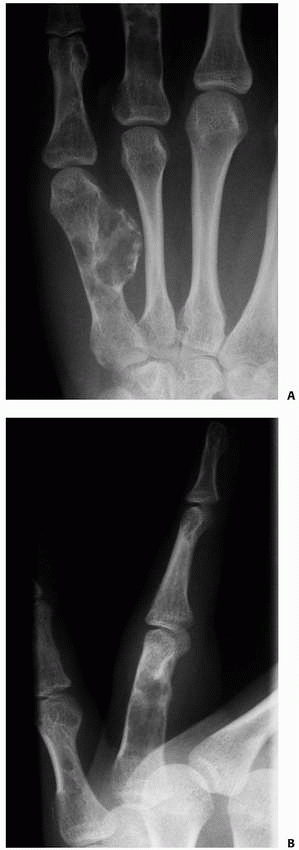

![]() |

FIGURE 8-5

The straight-method of assessing alignment about the MCP joint. The long axes of the metacarpal and proximal phalanx should align, as they do in this normal hand (A). If there is a fracture in the proximal phalanx, as in this patient’s opposite or injured hand (B,C), the axes will not be colinear (arrows). (Courtesy of Robert M. Campbell, Jr., MD.) |